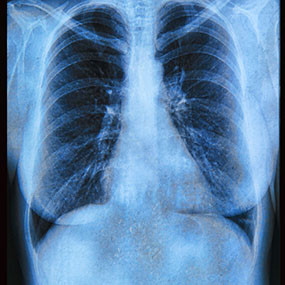

Nếu nhiễm trùng đường hô hấp hay cảm lạnh, cơn ho sẽ biến mất sau 1-2 tuần. Nhưng cơn ho dai dẳng, dù là ho khan hay có đờm, cũng có thể là dấu hiệu của ung thư phổi. Hãy đến khám bác sĩ ngay để được chụp X-quang và làm các xét nghiệm cần thiết khác.